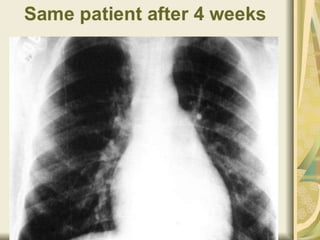

 Patient with fever, active arthritis or active carditis

 Patients with inflammation of the heart continue for the

• Antibiotics  Patientwith fever, active arthritis or active carditis should be rested in bed. Oral Penicillin: Phenoxypenicillin 500 mg 4 times daily for one week  preventive treatment  Phenoxypenicillin 250 mg twice daily continues until the child is at least 21 years old  If past age 20 to complete a minimum five-year course of preventive treatment.  Patients with inflammation of the heart continue for the rest of his life